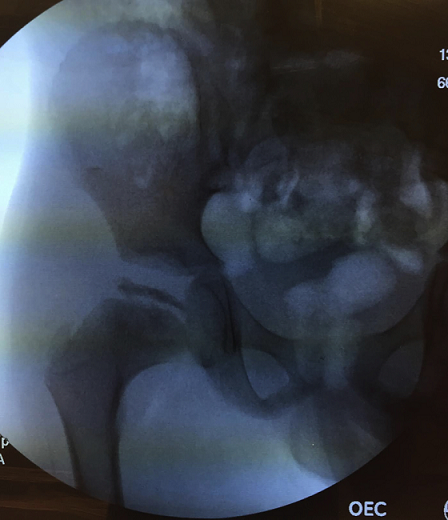

A 6-year-old boy presented with the recent development of a right sided limp. He had no known medical conditions. On examination, the patient had limited internal/external rotation and abduction of the right hip. He walked with a non-antalgic gait and was noted to have a positive Trendelenberg sign. Lower extremity radiographs (A) revealed flattening of the right proximal femoral epiphysis with greater than 50% collapse. Mild acetabular changes of the right hip were present; however, there was still concentric reduction of the right femoral head within the acetabulum. After a thorough discussion of management options, the patient received botulinum toxin injections along the adductor longus and gracilis muscles to resolve an adduction contracture. An arthrogram (B) demonstrated mild-moderate flattening of the femoral head with lateral femoral head extrusion, and moderate femoral-acetabular congruency. The patient was subsequently given a hip abduction orthosis for intermittent daytime and full nighttime bracing, and was instructed to continue stretching exercises daily. The parents were educated regarding the cyclical nature of the pathology, and that the prognosis is relatively improved in younger children with the potential to still remodel. Legg-Calvé-Perthes disease describesan idiopathic avascular necrosis of the proximal femoral epiphysis. Initial therapy includes maintenance of the femoral head within the acetabulum by an abduction splint. Additionally, daily abduction stretching exercises and physical therapy are recommended. Surgical containment can be achieved by a femoral osteotomy to redirect the involved portion within the acetabulum.